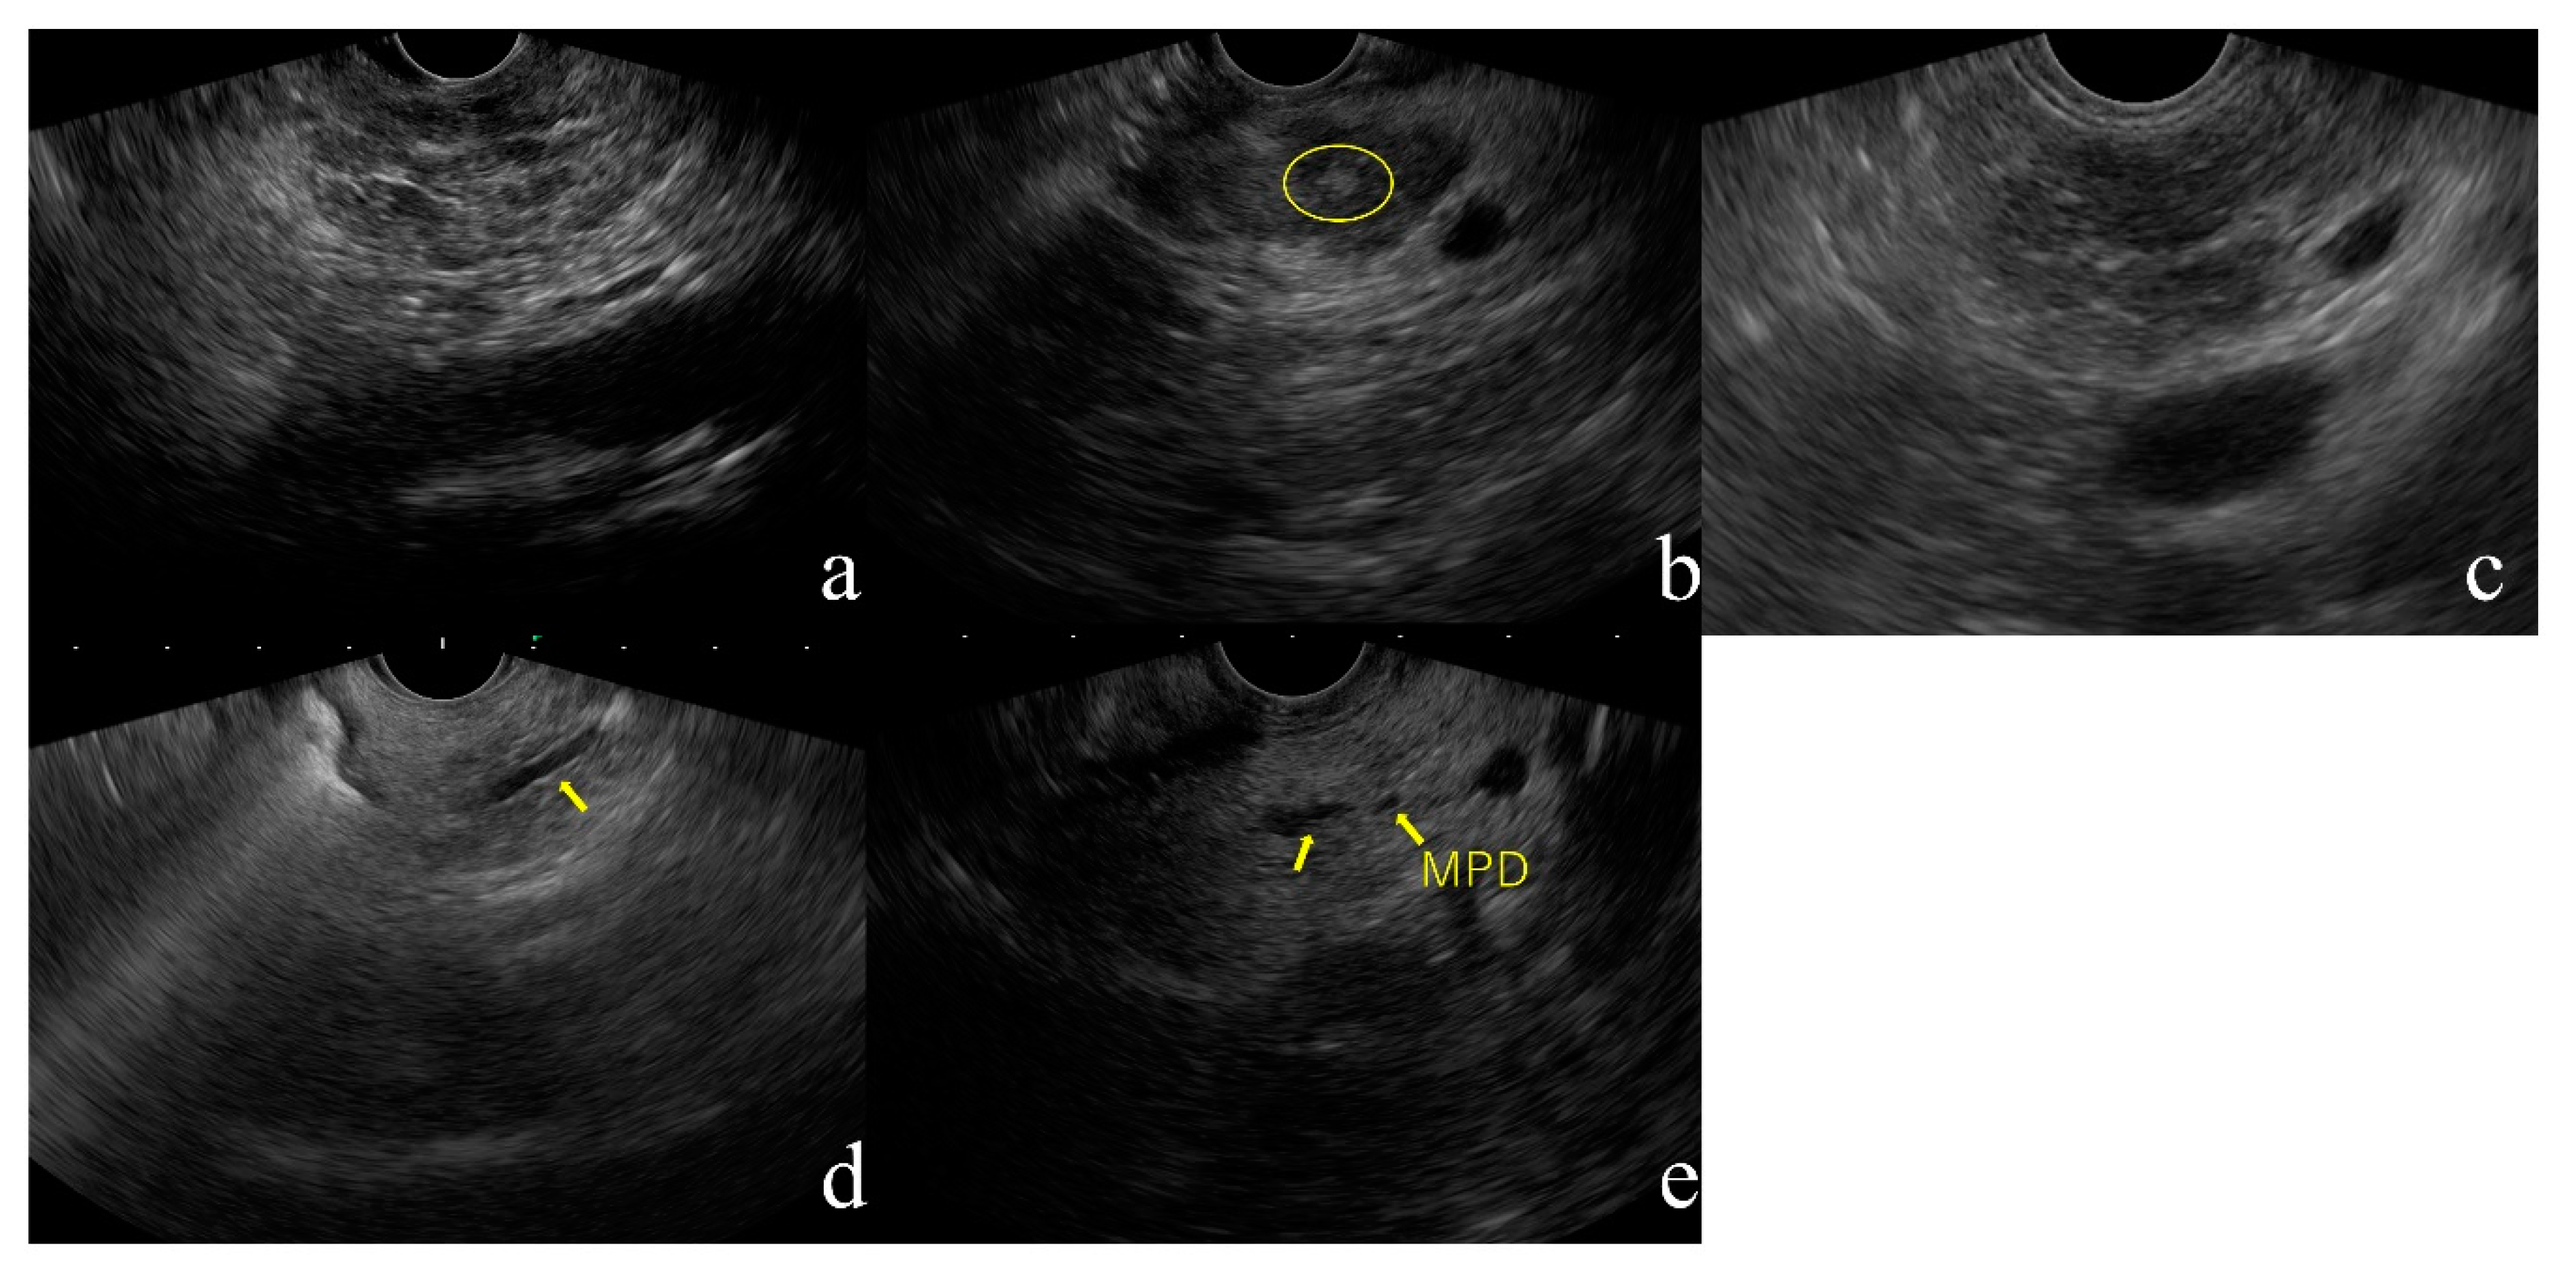

- Lobularity (Figure 1a)

- Hyperechoic foci without shadowing (Figure 1b)

- Strands (Figure 1c)

- Hyperechoic MPD margin (Figure 1d)

- Dilated side branches (Figure 1e)